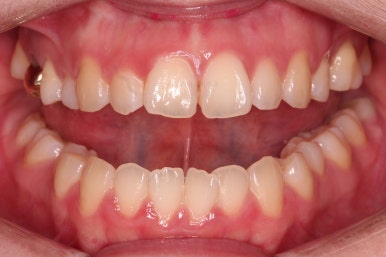

폭이 맞아지고 치아 배열을 조금 시행하니 송곳니 부분에서의 반대교합이 금새 개선된 것을 알 수 있으실거에요.

이렇게 측방으로의 반대교합만 개선이 되어도 턱관절에서의 불편감은 많이 줄어들게 됩니다.

전후 비교 해볼게요.

가지런한 느낌, 교합, 중앙선, 반대교합 등 모든 면에서 개선이 되었고요.